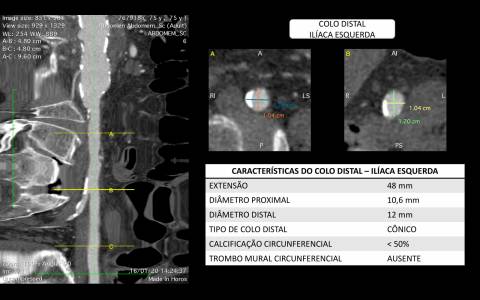

O estudo de angiotomografia evidenciou que as artérias iliacas externas e femorais apresentavam-se com muitas calcificações e ponto de estenose mais crítica em artéria ilíaca comum direita. Diante dos achados de imagem, foi optado por endoprotese de aorta abdominal de baixo perfil (Incraft – Cordis).